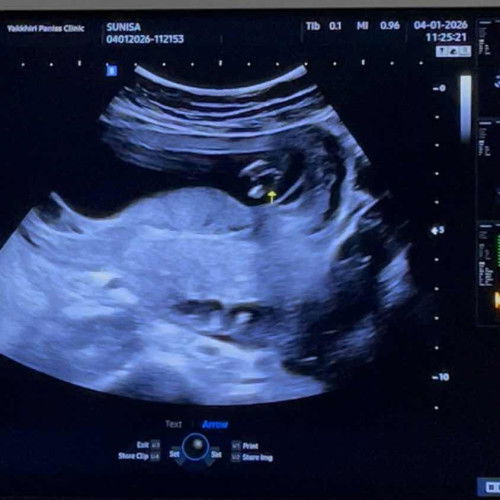

แม่ๆช่วยดูหน่อยค่ะว่าน้องผญ หรือ ผช หมอซาวให้แล้วแต่ยังไม่กล้าคอนเฟริม รอลุ้นผลนีฟอยู่ค่ะ ตอนซาว13วีค5วันค่ะ